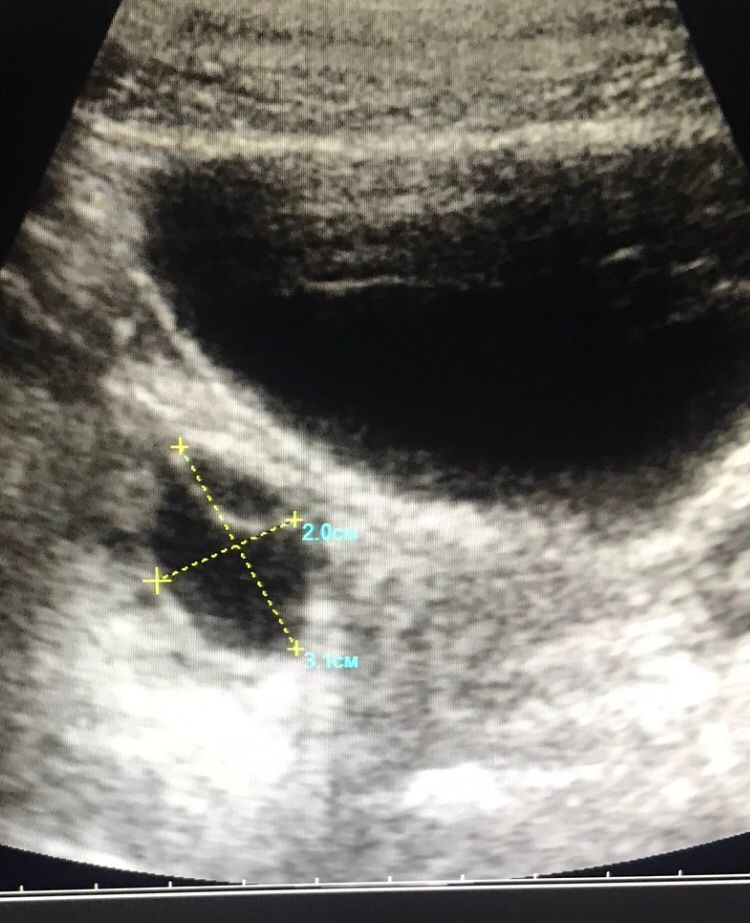

Киста с перегородкой

По идее, перегородка ничего не значит. Может быть фибриновый тяж, может слизистая так отвисает. Пока не вскрыть - не понятно. Лично я б не переживала. Столько всяких разных кист видела. Вот когда с взвесью или множественные тяжи - то тут ппц, плохо

Дашута, гинеколог на старом аппарате узи смотрел в среду,сказал,что ему все не нравится и отправил сдавать онкомаркеры,я сдала,переделала у другого узиста на новом аппарате ,он написал,что фолликулярные кисты. Одна с тонкой эхопозитивной перегородкой. У меня в дневнике есть пост,там фото,и,что в каждом яичнике по 3,4 фолликула. Brads2. Я конечно ужасно боюсь результатов. Почему такой разгон у них. Надо переделывать мрт?второй узист вообще сказал,забыть и ходить дальше и на узи через год

Здравствуйте. Как ваша ситуация разрешилась?у меня какая-то тоже полная попа по узи..перегородка в образовании,на каждом яичнике по кисте вроде,отправили на онкомаркеры сдавать..жду